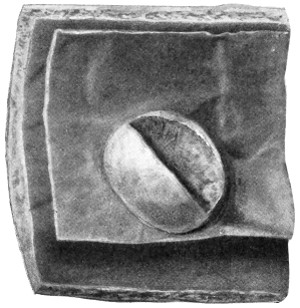

| 7. Hudson’s trephine | 20 |

Fig. 7. Hudson’s Trephine. Showing the usual method of using the spiral perforator, spiral follower, and enlarging burr.